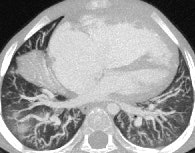

CT is vital for evaluating the central airway, mediastinal structures, and lung parenchyma, plus it's more sensitive than plain radiographs in detection of structural changes within the lungs, but CT examinations must be clinically justified by the referring clinician and radiologist.

MDCT using a low radiation dose protocol is the best diagnostic tool for assessing the central airway, cardiovascular and mediastinal abnormalities, and the lung parenchyma in children, and the relevant information can be acquired with a single-volumetric data set acquisition, she stated. Using thin-slice collimation acquisition with inherent isotropic resolution, the image data can be manipulated and reformatted to display 2D and 3D images with the same spatial resolution as the axial images, thus enhancing diagnostic accuracy and providing data that can be used in presurgical planning and patient management.